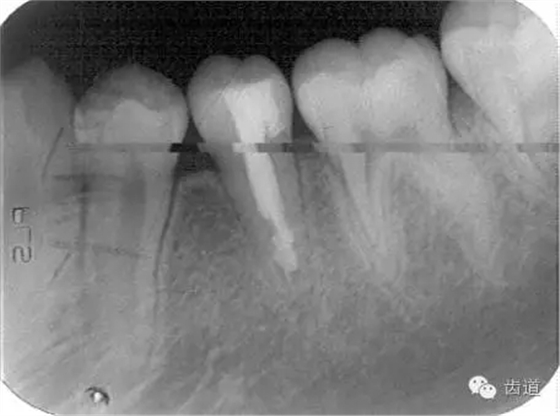

1.術(shù)前X線片

術(shù)后

術(shù)后199日

術(shù)后1084日